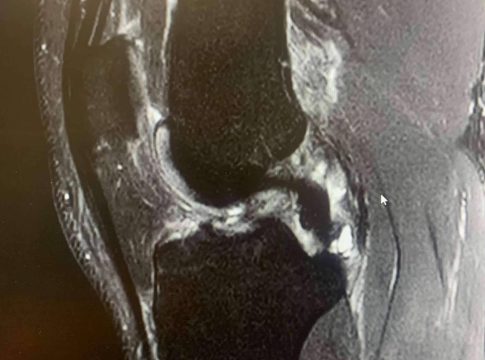

El ligamento cruzado anterior es una banda de tejido fuerte y resistente que se encuentra en la rodilla y juega un papel crucial tanto en la estabilidad como en la capacidad de control de esta articulación.

Las lesiones de LCA suelen ocurrir en situaciones en las que la rodilla está sometida a un estrés repentino y excesivo, sobre todo cuando la pierna está en apoyo y se somete a una torcedura en valgo (“metiendo la rodilla hacia dentro”) o con una torsión de la pierna hacia afuera con torsión interna del muslo, con la rodilla en flexión.

Inestabilidad articular: La sensación de que la rodilla se «mueve» o «falla» al apoyar puede ser un síntoma característico de una lesión del LCA. Se puede sentir que la rodilla no es tan estable como antes y que se desplaza incontrolablemente.

Limitación en el rango de movimiento: La lesión del LCA puede dificultar la capacidad de estirar y flexionar completamente la rodilla, lo que limita el rango de movimiento.